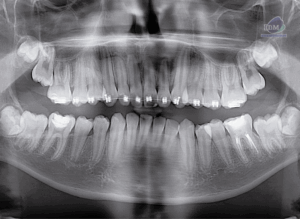

Paciente masculino de 25 años de edad acude al Instituto para una tomografía de macizo facial para la colocación de ortodoncia, a la evaluación de